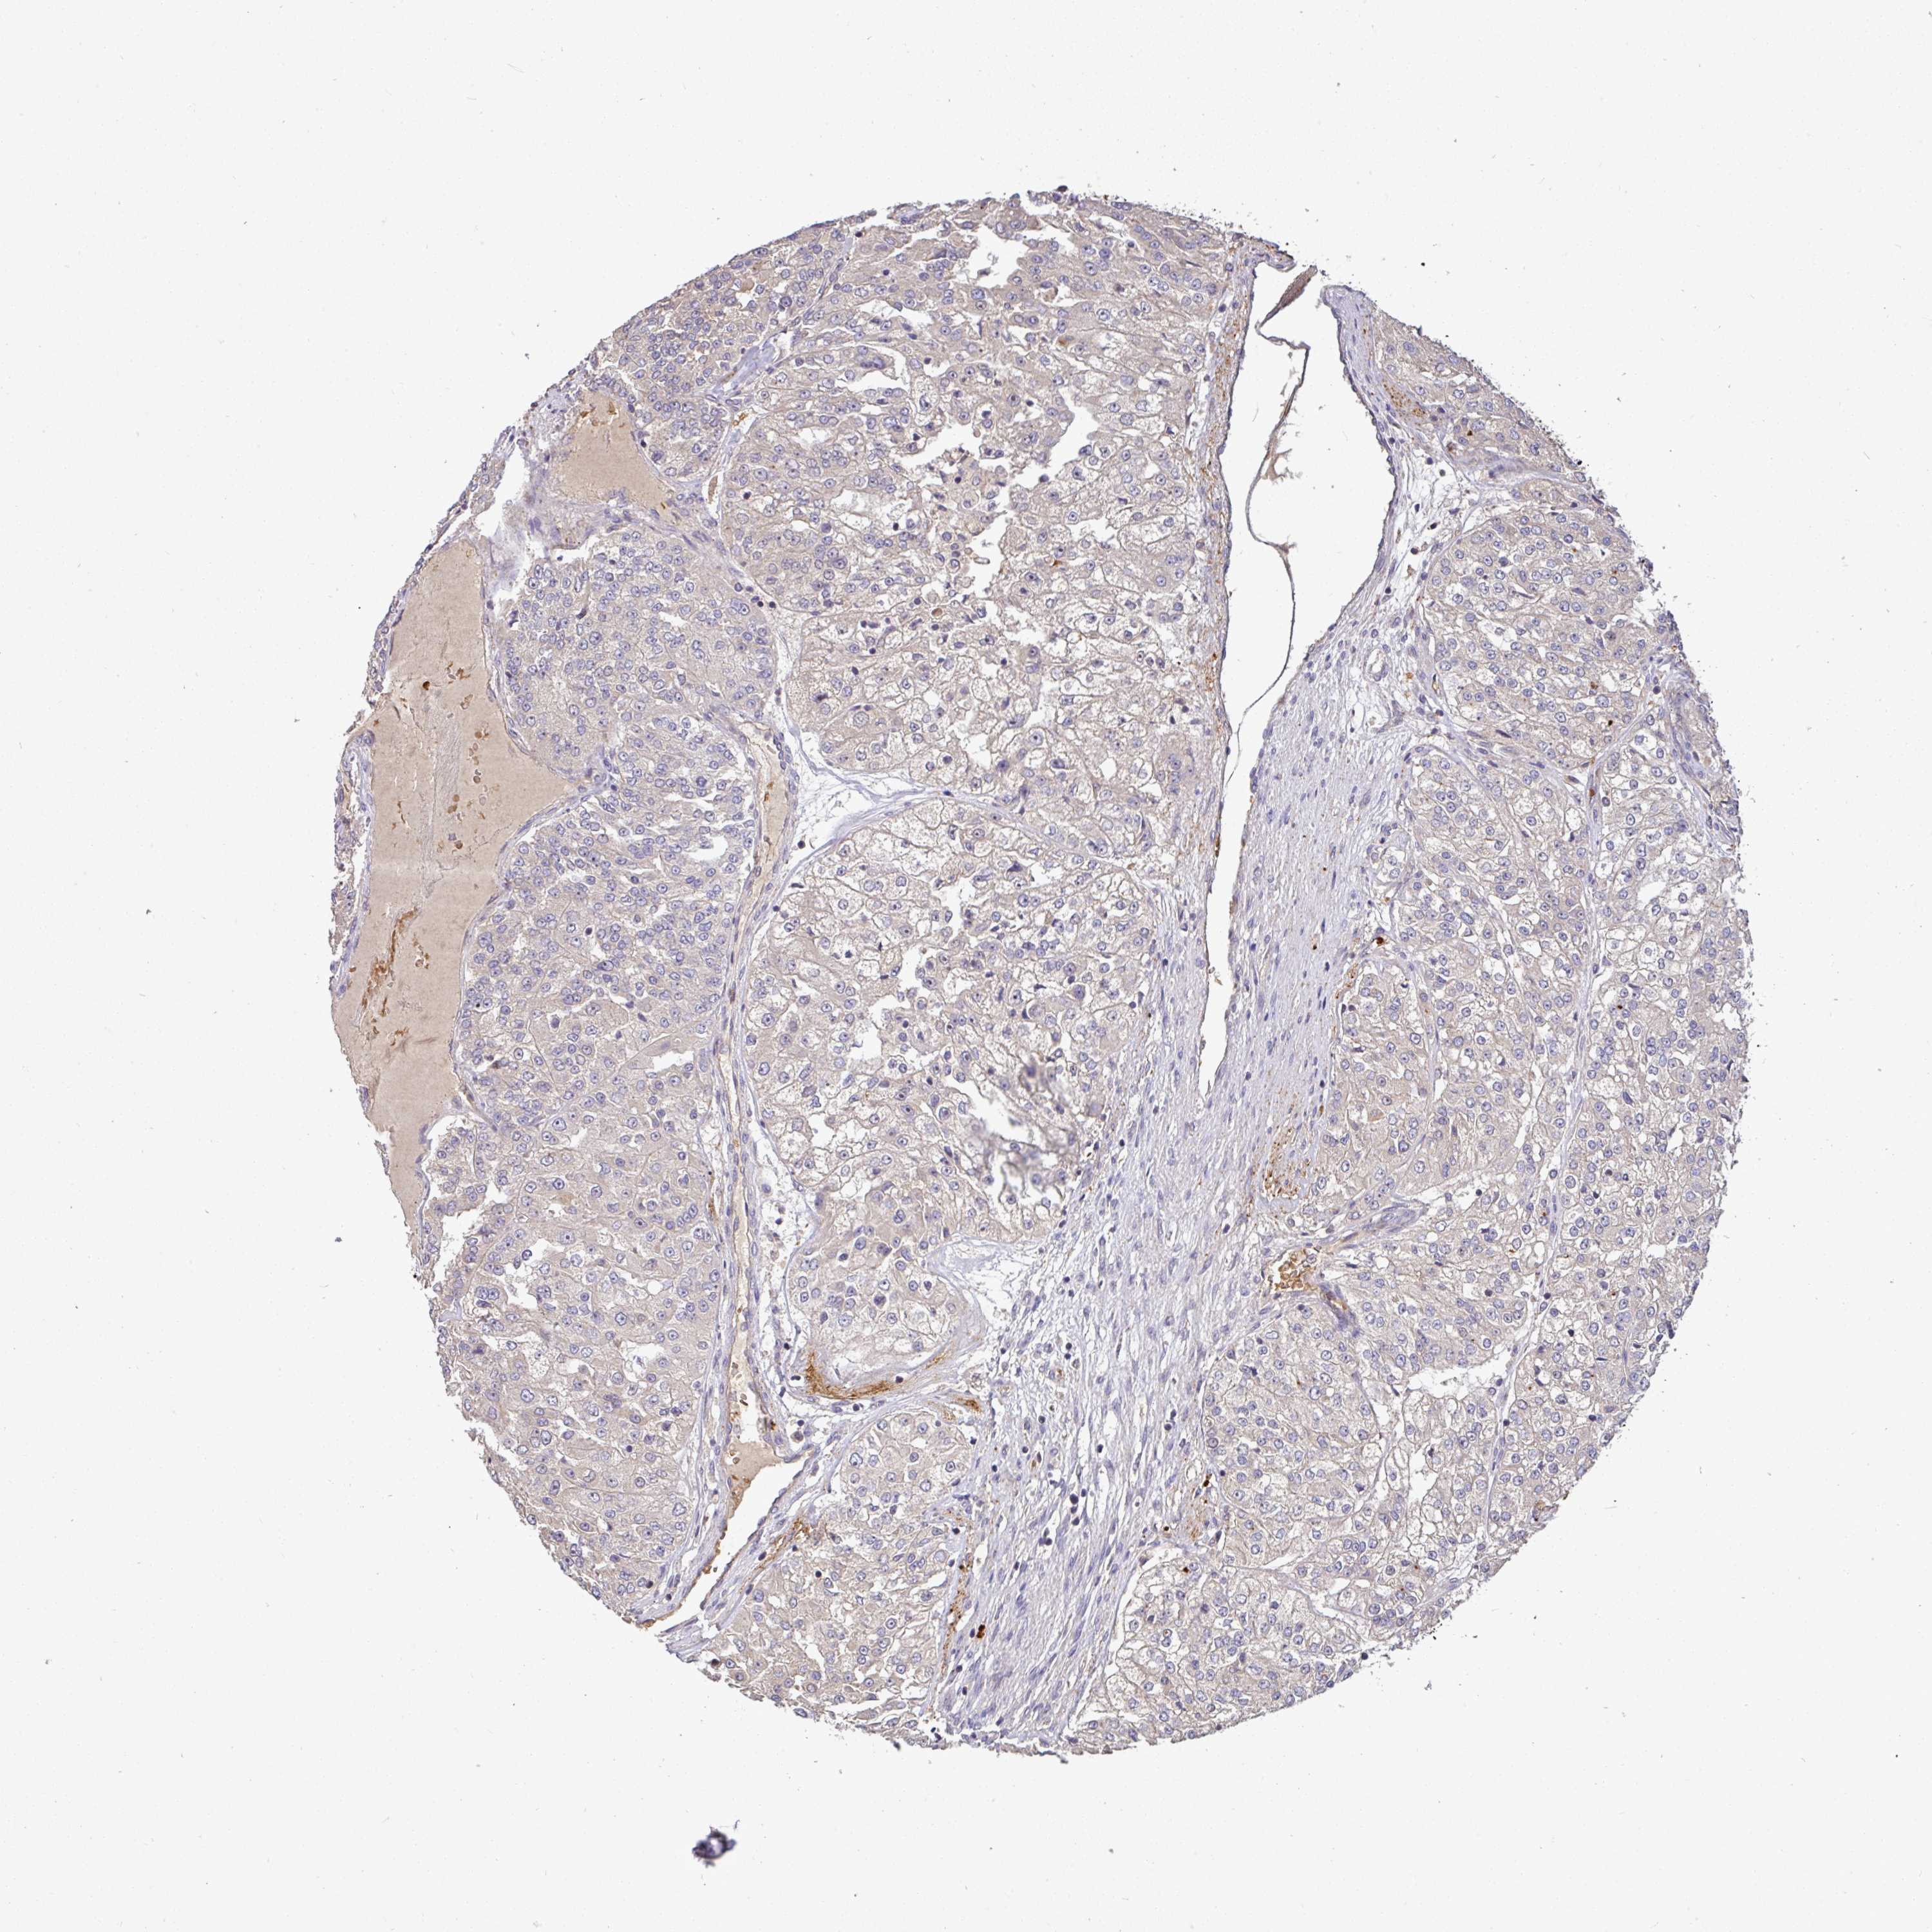

KIDNEY RENAL CLEAR CELL CARCINOMA (TCGA) - Interactive survival scatter ploti

The Survival Scatter plot shows the clinical status (i.e. dead or alive) for all individuals in the patient cohort, based on the same data that underlies the corresponding Kaplan-Meier plots. Patients that are alive at last time for follow-up are shown in blue and patients who have died during the study are shown in red.

The x-axis shows the expression levels (FPKM) of the investigated gene in the tumor tissue at the time of diagnosis. The y-axis shows the follow-up time after diagnosis (years). Both axes are complimented with kernel density curves demonstrating the data density over the axes. The top density plot shows the expression levels (FPKM) distribution among dead (red) and alive patients (blue). The right density plot shows the data density of the survived years of dead patients with high and low expression levels respectively, stratified using the cutoff indicated by the vertical dashed line through the Survival Scatter plot. This cutoff is automatically defined based on the FPKM cutoff that minimizes the p-score. The cutoff can be changed by dragging the vertical line or by entering a cutoff value in the square labeled "Current cut-off".

Under the Survival Scatter plot the p-score landscape (black curve; left axis) is shown together with dead median separation (red curve; right axis). Dead median separation is the difference in median mRNA expression between patients who have died with high and low expression, respectively. It is calculated as follows: median FPKM expression of dead patients with high expression - median FPKM expression of dead patients with low expression. This is intended to aid the user in visually exploring custom cutoffs and the associated p-scores and dead median separation.

Individual patient data is displayed and can be filtered by clicking on one or more of the category buttons on the top of the page. Categories describing expression level and patient information include: high, low, alive, dead, female, male and tumor stages. The scale of the x-axis can be toggled between linear and log-scale by clicking on the "x log" button. Mouse-over function shows TCGA ID, patient information and mRNA expression (FPKM) for each patient.

& Survival analysisi

Kaplan-Meier plots summarize results from analysis of correlation between mRNA expression level and patient survival. Patients were divided based on level of expression into one of the two groups "low" (under cut off) or "high" (over cut off). X-axis shows time for survival (years) and y-axis shows the probability of survival, where 1.0 corresponds to 100 percent.

C1QTNF9B is potential prognostic, high expression is favorable in Kidney Renal Clear Cell Carcinoma (TCGA)

: 0.53

Average pTPM 1.2

Number of samples 521